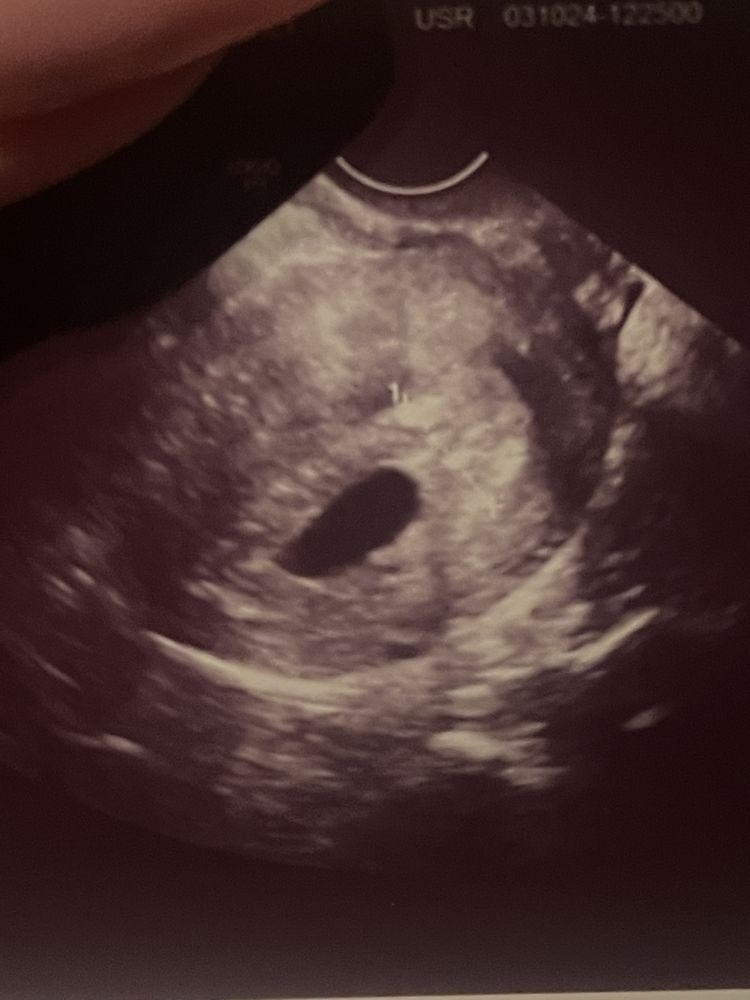

а сегодня пя18,5 но пя пустое, как это возможно я не понимаю

У вас даже желточного мешочка нет в плодном яйце😞

Тут как я поняла пусто? А жм есть?